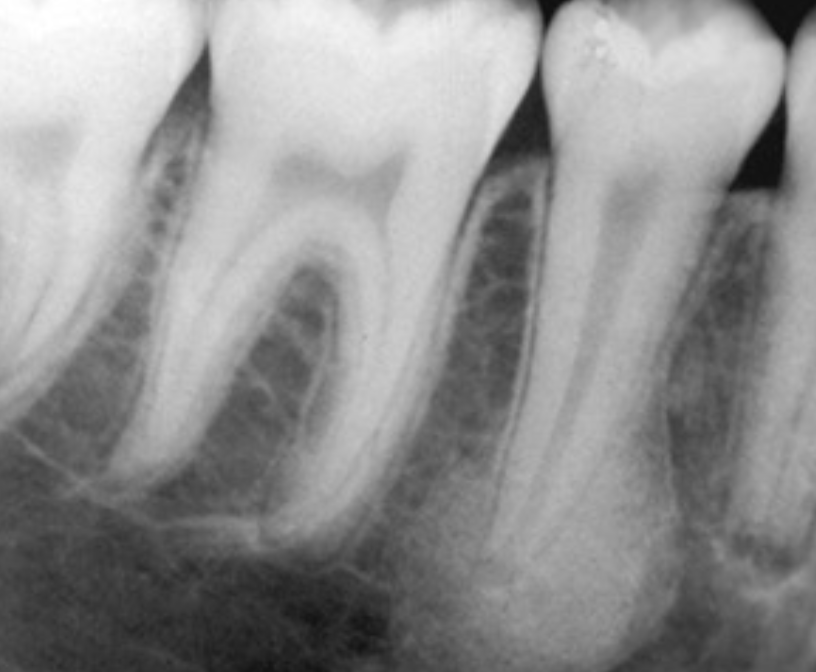

long-standing lesions → radiolucency at root apex with surrounding radiopacity

imaging appearance varies on disease stage and bone response

location → mostly apical, but can be accessory canals or root perforations and fractures

widening of PDL space

loss of lamina dura definition